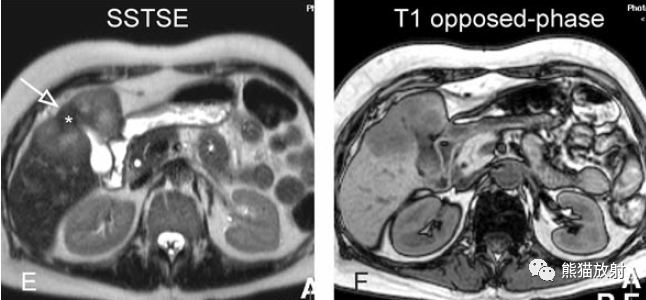

另一例膽囊癌,T2WI及增強延遲期顯示膽囊壁不均勻增厚并明顯強化。